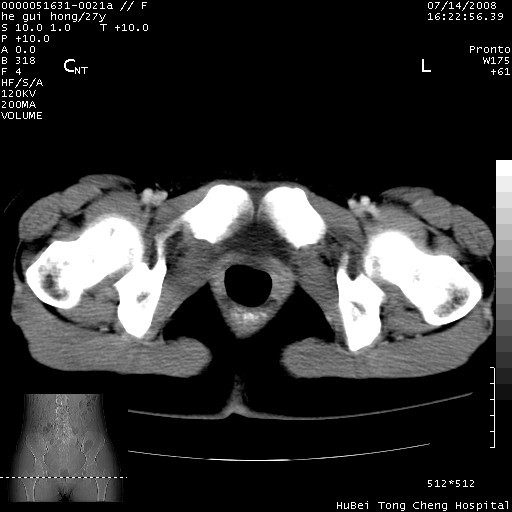

以下是引用杀毒软件在2008-7-20 8:03:00的发言:[br]支持双侧卵巢囊腺瘤可能性大!

以下是引用zjzjr在2008-7-20 13:36:00的发言:[br]双侧附件囊腺瘤可能性大!